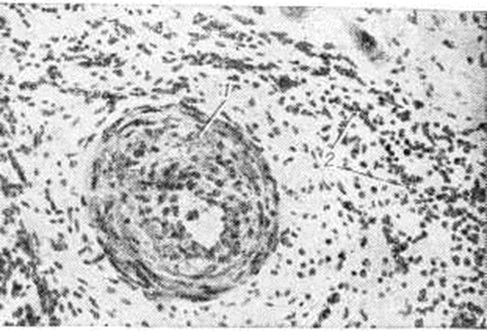

Гранулематозный (специфический) миокардит характеризуется наличием гранулемы (смотри полный свод знаний) в миокарде (рисунок 8). Он различен по происхождению, но чаще имеет инфекционную этиологию. Наиболее известны туберкулёзный, сифилитический, ревматический и грибковый гранулематозные Миокардит, а также Миокардит при саркоидозе.

Рис. 8. | ||

Гигантоклеточный миокардит гистологически характеризуется диффузным Миокардит с распространенными крупными очагами некроза, окаймлёнными клеточным инфильтратом с множеством гигантских клеток миогенного и гистиогенного происхождения (рисунок 9). Подобный по морфологический картине Миокардит описан при тимомах, протекающих с миастеническими кризами, при гранулематозе Вегенера, генерализованном саркоидозе. Гигантоклеточный Миокардит ранее ошибочно рассматривали как диффузный туберкулёзный Миокардит